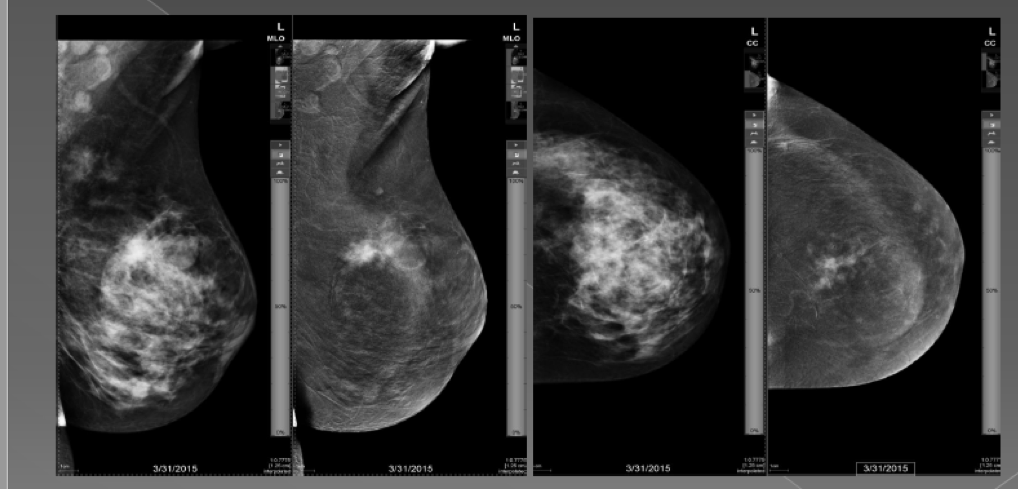

Endikasyon 1: Sol nipple'dan kanlı discharge. sol üst dış kadran 8 cm çapta yoğun segmental kontrast tutulumu. Nekrozu kribritform insitu duktal karsinom

Endikasyon 2: Meme kanserinin tanısı ve yaygınlığının değerlendirilmesinde Lobüler - CA

CESM aynı anda iki farklı görünüm oluşturacak spektral ileri veri teknolojisine sahiptir. Normal doku sinyallerinin söndüğü, yoğun süt bezinin örtüldüğü, sadece kontrast madde ile ortaya çıkan tümöral alanların parladığı görüntüler standart mamografi ile tamamiyle aynı pozisyonda elde edilir.